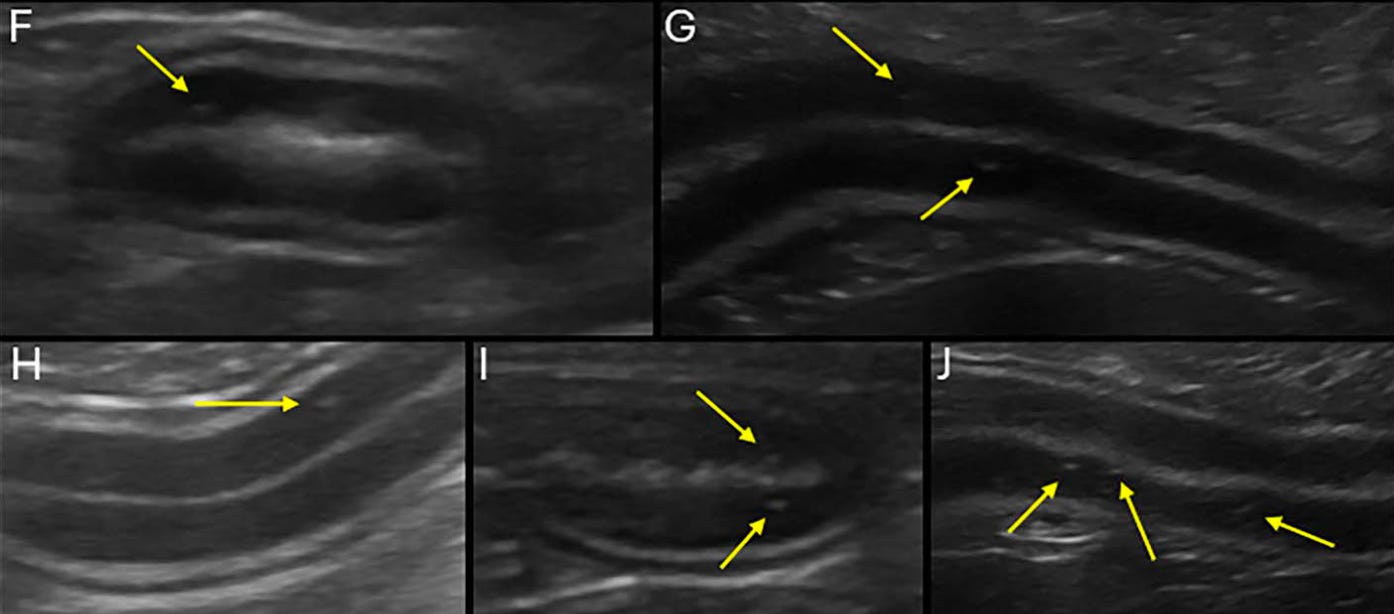

Diferentes grados de punteados hiperecogénicos de la mucosa: